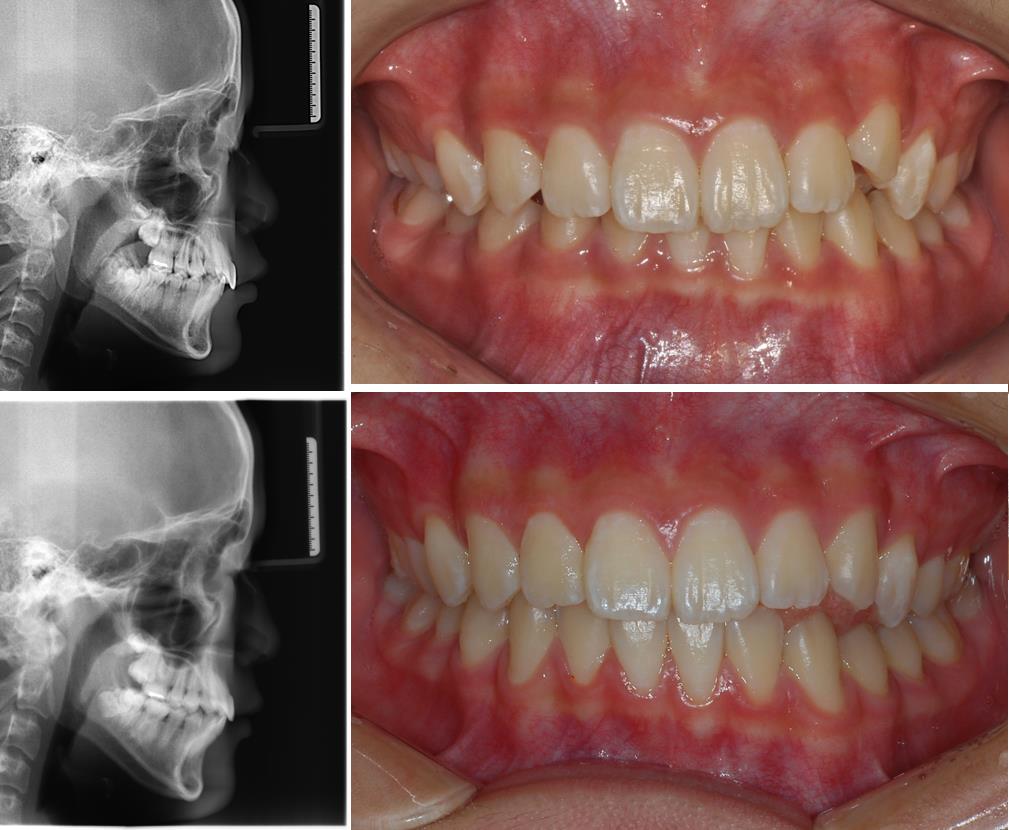

Does this look like ordinary orthodontic treatment to you?

Comparison between MCB-concept Invisalign and conventional Invisalign at other dental clinics .

UnderBite Treatment!!!